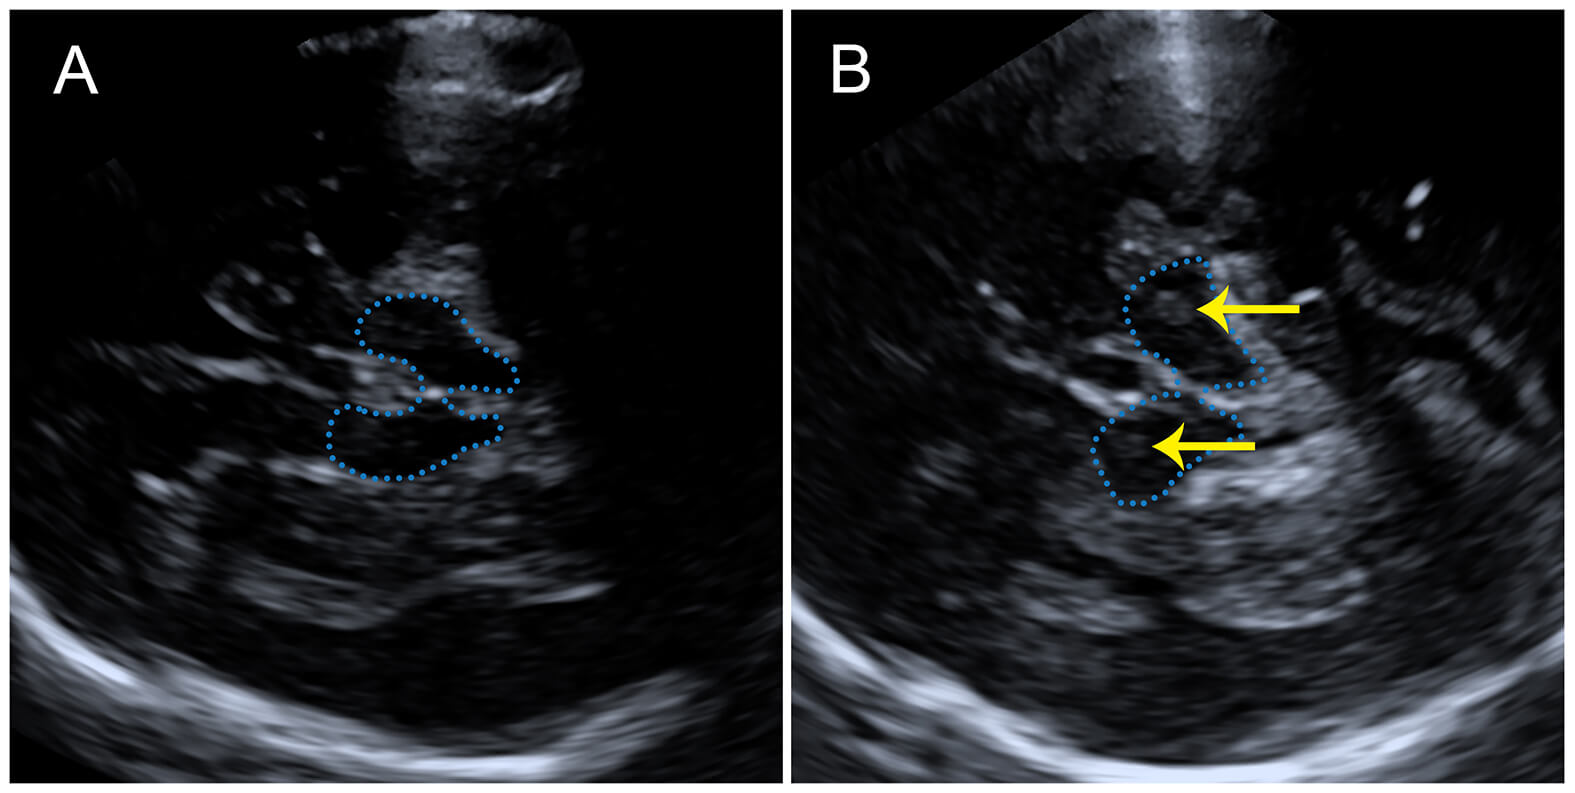

Fig. 2.

Transcranial ultrasonography showing butterfly-shaped midbrain and internal sonographic features. (A) No significant substantia nigra hyperechogenicity (SNH) is detected within the midbrain. (B) Focal SNH is visualized within the midbrain (yellow arrow). The blue dashed line outlines the midbrain region.